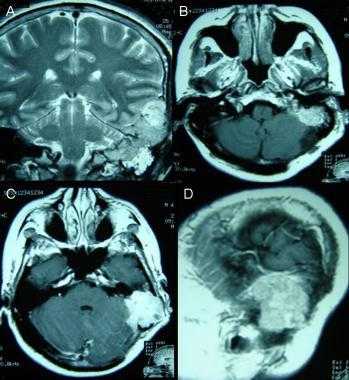

Менингиома височной области. На серии последовательных МР-изображений видно крупное образование правой височной области с паттерном контрастирования по типу «колеса со спицами», местным объемным воздействием, отеком окружающих тканей и гиперостозом подлежащей кости.

Атипичная с деструкцией пирамиды височной кости. На корональном Т2-взвешенном и контрастированном Т1-взвешенном МР-изображении виден быстрый рост конвекситального объемного образования в сторону намета мозжечка и пирамиды височной кости.